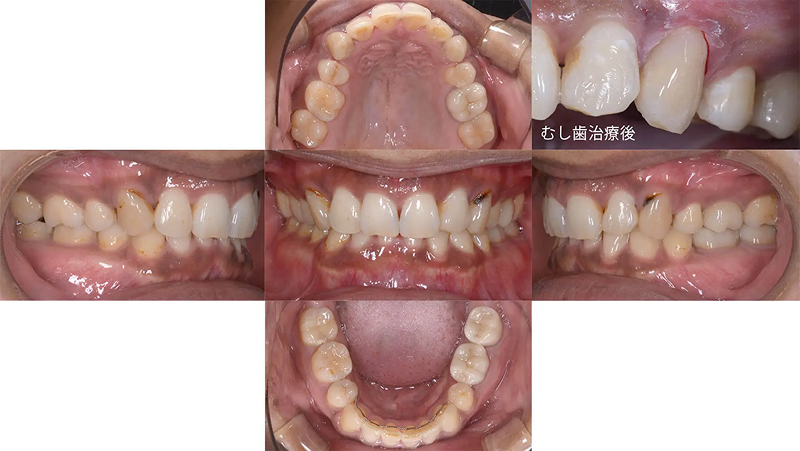

前歯の凸凹が著しい状態でした。清掃がしにくく、上顎側切歯がロックされていました。むし歯治療とともに矯正治療をすることになりました。診査の結果、歯列にスペースがないことがわかりました。口元をきれいにし、歯列を整えるには小臼歯4本抜歯が必要と診断しました。仕事をしながらなので、通院が少し大変でしたが、無事きれいな歯列を獲得できました。

初診 2014.10.16

矯正治療開始 2014.11.26

矯正治療終了 2016.7.12

ファイナル 2016.12.22

治療後2年半 2019.6.24

| 主訴 | 前歯の凸凹を治したい |

|---|---|

| 診断 | 両側アングル1級の叢生 |

| 矯正方法 | 小臼歯4本抜歯を伴うマルチブラケット |

| 矯正期間 | 20か月・21回 |

| 費用 | 746,000円(税別) |

| 調整料 | 月1回 5,000円(税別) |